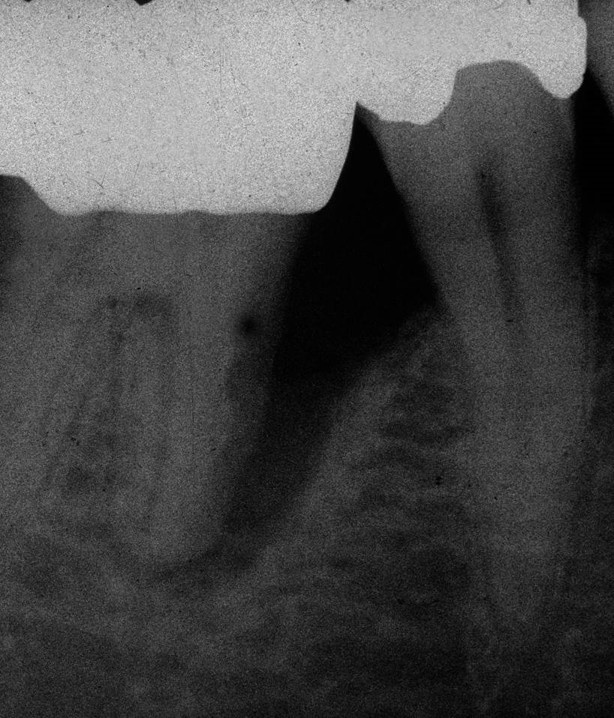

Durch eine Vielzahl von Studien konnte belegt werden, dass die Versorgung mit implantatgetragenem Zahnersatz eine bewährte Behandlungsoption darstellt. Gleichwohl zeigen viele Studien jedoch, dass – wie bei allen Therapiemaßnahmen auch – Komplikationen auftreten können. Diese haben im Allgemeinen biologische oder technische Ursachen. Als häufigste biologische Komplikation findet man die Mucositis (Abb. 1), die Entzündung der periimplantären Gewebe ohne Beteiligung des Alveolarknochens. Nach aktuellen Studien weisen ca. 30 % aller Implantate nach fünf Jahren eine Mucositis auf. Kommt es darüber hinaus zu einer Beteiligung des Alveolarknochens, liegt eine Periimplantitis vor (Abb. 2). Sie tritt nach fünf Jahren bei etwa 10 % der inkorporierten Implantate auf und ist durch den Verlust des periimplantären Alveolarknochens gekennzeichnet. Die Periimplantitis kann, je nach Schweregrad, zum kompletten Implantatverlust führen. Bei einem strategisch wichtigen Implantat kann daraus der Verlust der gesamten prothetischen Versorgung resultieren und eine operativ sowie finanziell aufwendige Neuversorgung erforderlich werden (Abb. 3).

Neben den biologischen Ursachen können auch technische Schwierigkeiten auftreten. Dabei ist die komplette Fraktur eines Implantats (Abb. 4) zweifellos die schwerwiegendste, sie tritt aber nur sehr selten auf. Häufiger sind Schraubenlockerungen und Schraubenfrakturen, wobei letztere in Abhängigkeit von der Lokalisation der Fraktur ebenfalls den Verlust eines Implantats zur Folge haben kann.

Eine absolute Extraktionsindikation stellt die Wurzellängsfraktur bei einwurzeligen Zähnen dar. Differenzierter zu betrachten ist die Wurzellängsfraktur eines mehrwurzeligen Zahnes. Bei entsprechend günstigen Voraussetzungen kann mitunter auch die Option einer Hemisektion in Betracht gezogen werden. In die Entscheidungsfindung sollten auch immer Überlegungen zur langfristigen Planung einfließen. Die prothetische Wertigkeit eines Molaren ist beispielsweise durch die Entfernung einer Wurzel deutlich herabgesetzt. Klinisch imponiert bei Längsfrakturen der sogenannte „Kamineffekt“. Bei zirkulär sonst unauffälligen Sondierungstiefen fällt man entlang des Frakturverlaufs mit der Messsonde in den osteolytisch entstandenen „Kamin“ (Abb. 13). Auch im hier dargestellten Fall (Abb. 16) war nach Auswertung aller relevanten Aspekte (Ursache, Prognose, langfristige prothetische Planung) die frühzeitige Extraktion Mittel der Wahl um die Voraussetzungen für eine anschließende Implantation nicht negativ zu beeinflussen.